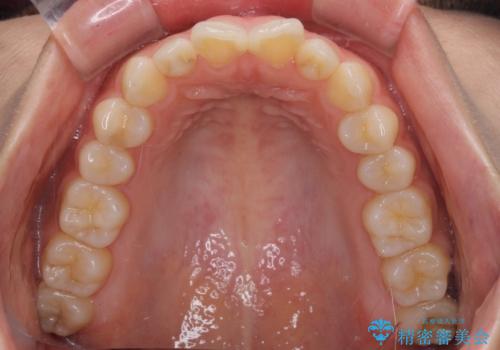

インビザラインを用いた上顎の部分矯正

- 上顎前歯の叢生を気にして来院された患者様です。

下顎前歯や上下奥歯の咬み合わせには殆ど問題がないため、上顎前歯のみを矯正する治療を提案しました。

ワイヤー装置でもインビザラインでも可能でしたが、前歯のみをきれいに排列するのであればインビザラインの方が仕上がりが良いので、インビザライン・ライトにて治療を行うこととしました。